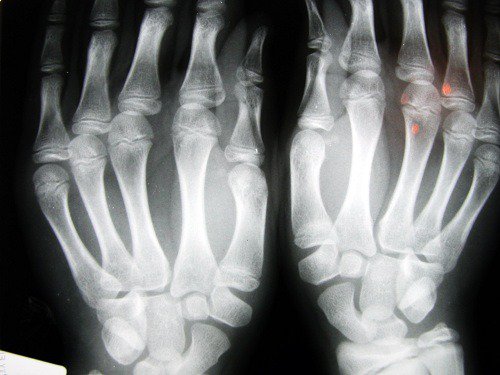

2. Risiko for artrose

En studie utført av universitetet i Nottingham (England) var i stand til å avgjøre at folk som hadde en kortere pekefinger hadde en høyere risiko for å utvikle problemer som artrose. Dette er relatert til mangel på østrogen og lav fysisk aktivitet, noe som spesielt rammer kvinner.